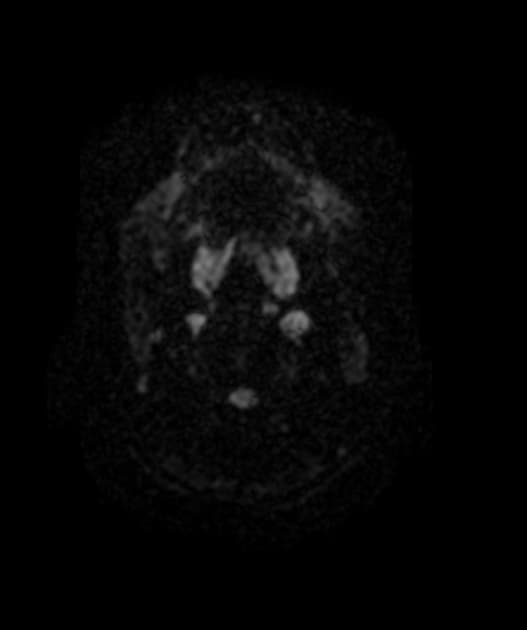

Axial ADC

Ảnh MRI khuếch tán (DWI, b=1000) cắt ngang tại thời điểm khởi phát cho thấy các vùng tăng tín hiệu đối xứng ở vùng trung tâm bán nguyệt hai bên, vùng chất trắng quanh não thất và chất trắng sâu ở thùy trán – đỉnh hai bên, cũng như ở thể chai và cuống não giữa hai bên, tương ứng với tín hiệu giảm trên bản đồ ADC, gợi ý hạn chế khuếch tán (restricted diffusion). Không thấy tín hiệu bất thường trên chuỗi xung FLAIR tại các vùng này. Các vùng bất thường có tín hiệu đồng tín hiệu (isointense) so với chất trắng trên ảnh T1W và không thấy ngấm thuốc trên ảnh T1W sau tiêm thuốc cản quang (không hiển thị).

Hình ảnh khuếch tán (DWI) đóng vai trò quan trọng cả trong giai đoạn cấp tính và theo dõi, để chứng minh tính hồi phục sau điều trị.

- "Các dãy hình ảnh DWI và ADC rất quan trọng để phát hiện sớm và theo dõi bệnh não chất trắng độc hồi phục."